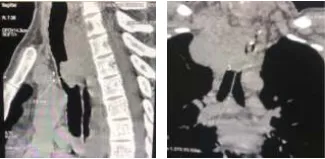

Here we present a case of central airway obstruction due to a tracheal tumor, managed successfully at Medicover Hospitals, Kakinada. A 38-year-old male came to our ER with symptoms of difficulty in breathing, cough, hemoptysis, difficulty in swallowing, and feeling of choking for one week. He had a history of squamous cell carcinoma esophagus for which he underwent surgery and radiation 2 years ago. He does not have any lifestyle habits. On examination, he has been in respiratory distress with inspiratory stridor. His general condition is poor, and his psychological condition is very low. His vitals at presentation were: blood pressure- 100/60, temperature- 99 F, respiratory rate- 28/min, oxygen saturation- 94% on room temperature, and pulse rate- 120/min. Immediate CT chest done showed upper mediastinal growth around the esophagus extending anteriorly causing near-complete occlusion of the tracheal lumen (>80). Arterial blood gas (ABG) showed respiratory alkalosis.

After providing general anesthesia, the patient’s head was d positioned in a "sniffing" position,and intubation was done directly with a rigid 6 Medicover Hospials - Kakinada HOSPITALS bronchoscope (Novatech, Tracheoscopy 14 mm O.D, Novatech SA, La Ciotat, France) under visualization. Thetrachea showed extrinsic luminal compression and tumor invasion into the lumen causing near-total occlusion of the trachea at mid-level. After injecting 1% adrenaline perilesional, mechanical debulking was done by scoring with rigid scope and tumor extracted piecemeal.Hemostasis was secured by the tamponade effect of tracheoscopy followed by electrocauterization of the tumor base. Near normal patency of tracheal lumen was achieved. Given extrinsic compression by the tumor, a self-expandable metallic stent (Otomed, fully covered, 16x 80 mm) was deployed using flexible bronchoscope guidance through the rigid scope.